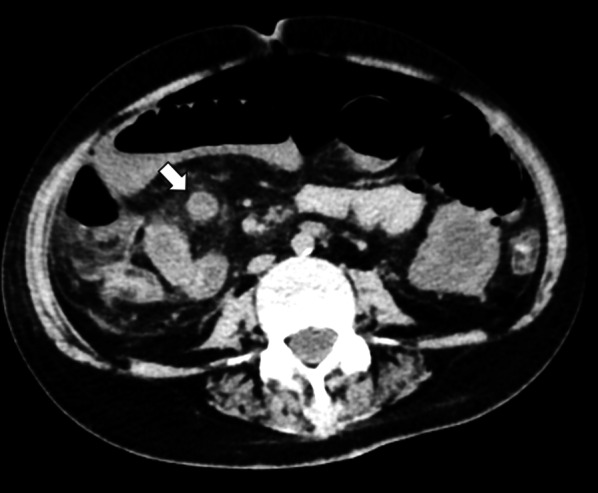

A 56-year-old woman diagnosed with galactosialidosis (β-galactosidase-neuraminidase deficiency) presented with vomiting. At admission, her general condition was poor, with a pulse rate of 90 bpm, blood pressure 110/60 mmHg, and oxygen saturation 100% without oxygen flow. On a physical examination she showed muscular defense over the whole abdomen. The laboratory test results on admission were as follows: red blood cell count, 488 × 106 cells/μL; hemoglobin 13.5 g/dL; leukocyte count, 6400 cells/μL; platelet count, 15.6 × 104 cells/μL; aspartate aminotransferase, 20U/L; alanine aminotransferase, 7 U/L; and C-reactive protein, 12.1 mg/dL. Abdominal X-ray photograph revealed a large amount of gas over most of the abdomen. Peritonitis due to perforation of the intestine was diagnosed based on the free air and dilated loop of the small bowel found on contrast-enhanced computed tomography (Fig. 1).

Fig. 1.

Computed tomography coronal view image obtained free air and a right quadrant heterogeneous mass within the loop of ileum (close arrows)